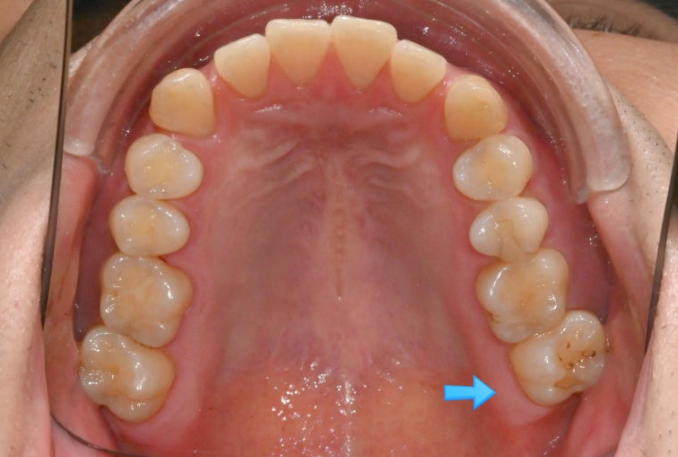

위 어금니는 배열에서 바깥으로 나가있고

아래 어금니는 안으로 쓰러져 있습니다.

가위교합의 빠른 해결을 위한 입천장의 교정용 나사도 썼습니다.

안으로 쓰러져 있던 큰어금니도 잘 세워졌고 가위교합도 해소가 되었습니다.

쓰러진 큰어금니가 잘 섰습니다.

가위교합의 개선으로 서로 엇갈려 물리지 못하던 큰어금니가 이제 잘 교합이 됩니다.